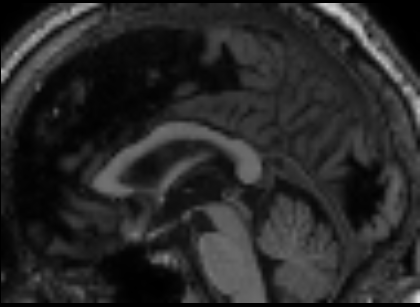

In summary, we consider a global view of data and a single GP which is specified with multiple covariance functions and aimed at single task learning. Despite the global view, the subtlety of MKL-AsRD should be noted. We wish to exploit the locality information in order to better capture the spatial patterns of brain atrophy. In this regard, we consider the portions of high-dimensional inputs, instead of the clusters obtained by an analysis of the joint feature space (Figure 1).

X= x1,1 x1,2 x1,3 x1,d x1,D xk,1 xk,2 xk,3 xk,d xk,D xN,1 xN,2 xN,3 xN,d xN,D []local viewglobal viewsubspace𝑋 subscript𝑥11 subscript𝑥12 subscript𝑥13 subscript𝑥1𝑑 subscript𝑥1𝐷 subscript𝑥𝑘1 subscript𝑥𝑘2 subscript𝑥𝑘3 subscript𝑥𝑘𝑑 subscript𝑥𝑘𝐷 subscript𝑥𝑁1 subscript𝑥𝑁2 subscript𝑥𝑁3 subscript𝑥𝑁𝑑 subscript𝑥𝑁𝐷 fragments[fragments]local viewglobal viewsubspaceX=\leavevmode\hbox to315.95pt{\vbox to131.21pt{\pgfpicture\makeatletter\hbox{\hskip 179.73059pt\lower-66.34442pt\hbox to0.0pt{\pgfsys@beginscope\pgfsys@invoke{ }\definecolor{pgfstrokecolor}{rgb}{0,0,0}\pgfsys@color@rgb@stroke{0}{0}{0}\pgfsys@invoke{ }\pgfsys@color@rgb@fill{0}{0}{0}\pgfsys@invoke{ }\pgfsys@setlinewidth{0.4pt}\pgfsys@invoke{ }\nullfont\hbox to0.0pt{\pgfsys@beginscope\pgfsys@invoke{ } {}{}{}{{}}{{}}{{}}{ {}}{{}}\hbox{\hbox{\hbox{\hbox{{\pgfsys@beginscope\pgfsys@invoke{ }{\offinterlineskip{}{}{{{}}{{}}{{}}{{}}{{}}{{}}{{}}{{}}{{}}{{}}{{}}{{}}{{}}{{}}{{}}{{}}{{}}{{}}{{}}{{}}{{}}{{}}{{}}{{}}{{}}{{}}{{}}{{}}{{}}{{}}{{}}{{}}{{}}{{}}{{}}}{{{}}}{{}{}{{ {}{}}}{ {}{}} {{}{{}}}{{}{}}{}{{}{}} { }{{{{}}\pgfsys@beginscope\pgfsys@invoke{ }\pgfsys@transformcm{1.0}{0.0}{0.0}{1.0}{-127.13118pt}{-57.0295pt}\pgfsys@invoke{ }\hbox{\vbox{\halign{\pgf@matrix@init@row\pgf@matrix@step@column{\pgf@matrix@startcell#\pgf@matrix@endcell}&#\pgf@matrix@padding&&\pgf@matrix@step@column{\pgf@matrix@startcell#\pgf@matrix@endcell}&#\pgf@matrix@padding\cr\hfil\hskip 18.33302pt\hbox{{\pgfsys@beginscope\pgfsys@invoke{ }{{}}\hbox{\hbox{{\pgfsys@beginscope\pgfsys@invoke{ }{{}{}{{ {}{}}}{ {}{}} {{}{{}}}{{}{}}{}{{}{}} { }{{{{}}\pgfsys@beginscope\pgfsys@invoke{ }\pgfsys@transformcm{1.0}{0.0}{0.0}{1.0}{-15.00002pt}{0.0pt}\pgfsys@invoke{ }\hbox{{\definecolor{pgfstrokecolor}{rgb}{0,0,0}\pgfsys@color@rgb@stroke{0}{0}{0}\pgfsys@invoke{ }\pgfsys@color@rgb@fill{0}{0}{0}\pgfsys@invoke{ }\hbox{\minipage[t]{30.00005pt}\leavevmode\hbox{}${x_{1,1}}$\endminipage} }}\pgfsys@invoke{\lxSVG@closescope }\pgfsys@endscope}}} \pgfsys@invoke{\lxSVG@closescope }\pgfsys@endscope}}} \pgfsys@invoke{\lxSVG@closescope }\pgfsys@endscope{}}}&\hskip 18.33302pt\hfil&\hfil\hskip 17.93303pt\hbox{{\pgfsys@beginscope\pgfsys@invoke{ }{{}}\hbox{\hbox{{\pgfsys@beginscope\pgfsys@invoke{ }{{}{}{{ {}{}}}{ {}{}} {{}{{}}}{{}{}}{}{{}{}} { }{{{{}}\pgfsys@beginscope\pgfsys@invoke{ }\pgfsys@transformcm{1.0}{0.0}{0.0}{1.0}{-15.00002pt}{0.0pt}\pgfsys@invoke{ }\hbox{{\definecolor{pgfstrokecolor}{rgb}{0,0,0}\pgfsys@color@rgb@stroke{0}{0}{0}\pgfsys@invoke{ }\pgfsys@color@rgb@fill{0}{0}{0}\pgfsys@invoke{ }\hbox{\minipage[t]{30.00005pt}\leavevmode\hbox{}${x_{1,2}}$\endminipage} }}\pgfsys@invoke{\lxSVG@closescope }\pgfsys@endscope}}} \pgfsys@invoke{\lxSVG@closescope }\pgfsys@endscope}}} \pgfsys@invoke{\lxSVG@closescope }\pgfsys@endscope{}}}&\hskip 18.33302pt\hfil&\hfil\hskip 17.93303pt\hbox{{\pgfsys@beginscope\pgfsys@invoke{ }{{}}\hbox{\hbox{{\pgfsys@beginscope\pgfsys@invoke{ }{{}{}{{ {}{}}}{ {}{}} {{}{{}}}{{}{}}{}{{}{}} { }{{{{}}\pgfsys@beginscope\pgfsys@invoke{ }\pgfsys@transformcm{1.0}{0.0}{0.0}{1.0}{-15.00002pt}{0.0pt}\pgfsys@invoke{ }\hbox{{\definecolor{pgfstrokecolor}{rgb}{0,0,0}\pgfsys@color@rgb@stroke{0}{0}{0}\pgfsys@invoke{ }\pgfsys@color@rgb@fill{0}{0}{0}\pgfsys@invoke{ }\hbox{\minipage[t]{30.00005pt}\leavevmode\hbox{}${x_{1,3}}$\endminipage} }}\pgfsys@invoke{\lxSVG@closescope }\pgfsys@endscope}}} \pgfsys@invoke{\lxSVG@closescope }\pgfsys@endscope}}} \pgfsys@invoke{\lxSVG@closescope }\pgfsys@endscope{}}}&\hskip 18.33302pt\hfil&\hfil\hskip 17.93303pt\hbox{{\pgfsys@beginscope\pgfsys@invoke{ }{{}}\hbox{\hbox{{\pgfsys@beginscope\pgfsys@invoke{ }{{}{}{{ {}{}}}{ {}{}} {{}{{}}}{{}{}}{}{{}{}} { }{{{{}}\pgfsys@beginscope\pgfsys@invoke{ }\pgfsys@transformcm{1.0}{0.0}{0.0}{1.0}{-15.00002pt}{0.0pt}\pgfsys@invoke{ }\hbox{{\definecolor{pgfstrokecolor}{rgb}{0,0,0}\pgfsys@color@rgb@stroke{0}{0}{0}\pgfsys@invoke{ }\pgfsys@color@rgb@fill{0}{0}{0}\pgfsys@invoke{ }\hbox{\minipage[t]{30.00005pt}\leavevmode\hbox{}${\cdots}$\endminipage} }}\pgfsys@invoke{\lxSVG@closescope }\pgfsys@endscope}}} \pgfsys@invoke{\lxSVG@closescope }\pgfsys@endscope}}} \pgfsys@invoke{\lxSVG@closescope }\pgfsys@endscope{}}}&\hskip 18.33302pt\hfil&\hfil\hskip 17.93303pt\hbox{{\pgfsys@beginscope\pgfsys@invoke{ }{{}}\hbox{\hbox{{\pgfsys@beginscope\pgfsys@invoke{ }{{}{}{{ {}{}}}{ {}{}} {{}{{}}}{{}{}}{}{{}{}} { }{{{{}}\pgfsys@beginscope\pgfsys@invoke{ }\pgfsys@transformcm{1.0}{0.0}{0.0}{1.0}{-15.00002pt}{0.0pt}\pgfsys@invoke{ }\hbox{{\definecolor{pgfstrokecolor}{rgb}{0,0,0}\pgfsys@color@rgb@stroke{0}{0}{0}\pgfsys@invoke{ }\pgfsys@color@rgb@fill{0}{0}{0}\pgfsys@invoke{ }\hbox{\minipage[t]{30.00005pt}\leavevmode\hbox{}${x_{1,d}}$\endminipage} }}\pgfsys@invoke{\lxSVG@closescope }\pgfsys@endscope}}} \pgfsys@invoke{\lxSVG@closescope }\pgfsys@endscope}}} \pgfsys@invoke{\lxSVG@closescope }\pgfsys@endscope{}}}&\hskip 18.33302pt\hfil&\hfil\hskip 17.93303pt\hbox{{\pgfsys@beginscope\pgfsys@invoke{ }{{}}\hbox{\hbox{{\pgfsys@beginscope\pgfsys@invoke{ }{{}{}{{ {}{}}}{ {}{}} {{}{{}}}{{}{}}{}{{}{}} { }{{{{}}\pgfsys@beginscope\pgfsys@invoke{ }\pgfsys@transformcm{1.0}{0.0}{0.0}{1.0}{-15.00002pt}{0.0pt}\pgfsys@invoke{ }\hbox{{\definecolor{pgfstrokecolor}{rgb}{0,0,0}\pgfsys@color@rgb@stroke{0}{0}{0}\pgfsys@invoke{ }\pgfsys@color@rgb@fill{0}{0}{0}\pgfsys@invoke{ }\hbox{\minipage[t]{30.00005pt}\leavevmode\hbox{}${\cdots}$\endminipage} }}\pgfsys@invoke{\lxSVG@closescope }\pgfsys@endscope}}} \pgfsys@invoke{\lxSVG@closescope }\pgfsys@endscope}}} \pgfsys@invoke{\lxSVG@closescope }\pgfsys@endscope{}}}&\hskip 18.33302pt\hfil&\hfil\hskip 17.93303pt\hbox{{\pgfsys@beginscope\pgfsys@invoke{ }{{}}\hbox{\hbox{{\pgfsys@beginscope\pgfsys@invoke{ }{{}{}{{ {}{}}}{ {}{}} {{}{{}}}{{}{}}{}{{}{}} { }{{{{}}\pgfsys@beginscope\pgfsys@invoke{ }\pgfsys@transformcm{1.0}{0.0}{0.0}{1.0}{-15.00002pt}{0.0pt}\pgfsys@invoke{ }\hbox{{\definecolor{pgfstrokecolor}{rgb}{0,0,0}\pgfsys@color@rgb@stroke{0}{0}{0}\pgfsys@invoke{ }\pgfsys@color@rgb@fill{0}{0}{0}\pgfsys@invoke{ }\hbox{\minipage[t]{30.00005pt}\leavevmode\hbox{}${x_{1,D}}$\endminipage} }}\pgfsys@invoke{\lxSVG@closescope }\pgfsys@endscope}}} \pgfsys@invoke{\lxSVG@closescope }\pgfsys@endscope}}} \pgfsys@invoke{\lxSVG@closescope }\pgfsys@endscope}}&\hskip 18.33302pt\hfil\cr\vskip-0.4pt\cr\hfil\hskip 18.33302pt\hbox{{\pgfsys@beginscope\pgfsys@invoke{ }{{}}\hbox{\hbox{{\pgfsys@beginscope\pgfsys@invoke{ }{{}{}{{ {}{}}}{ {}{}} {{}{{}}}{{}{}}{}{{}{}} { }{{{{}}\pgfsys@beginscope\pgfsys@invoke{ }\pgfsys@transformcm{1.0}{0.0}{0.0}{1.0}{-15.00002pt}{0.0pt}\pgfsys@invoke{ }\hbox{{\definecolor{pgfstrokecolor}{rgb}{0,0,0}\pgfsys@color@rgb@stroke{0}{0}{0}\pgfsys@invoke{ }\pgfsys@color@rgb@fill{0}{0}{0}\pgfsys@invoke{ }\hbox{\minipage[t]{30.00005pt}\leavevmode\hbox{}${\vdots}$\endminipage} }}\pgfsys@invoke{\lxSVG@closescope }\pgfsys@endscope}}} \pgfsys@invoke{\lxSVG@closescope }\pgfsys@endscope}}} \pgfsys@invoke{\lxSVG@closescope }\pgfsys@endscope}}&\hskip 18.33302pt\hfil&\hfil\hskip 17.93303pt\hbox{{\pgfsys@beginscope\pgfsys@invoke{ }{{}}\hbox{\hbox{{\pgfsys@beginscope\pgfsys@invoke{ }{{}{}{{ {}{}}}{ {}{}} {{}{{}}}{{}{}}{}{{}{}} { }{{{{}}\pgfsys@beginscope\pgfsys@invoke{ }\pgfsys@transformcm{1.0}{0.0}{0.0}{1.0}{-15.00002pt}{0.0pt}\pgfsys@invoke{ }\hbox{{\definecolor{pgfstrokecolor}{rgb}{0,0,0}\pgfsys@color@rgb@stroke{0}{0}{0}\pgfsys@invoke{ }\pgfsys@color@rgb@fill{0}{0}{0}\pgfsys@invoke{ }\hbox{\minipage[t]{30.00005pt}\leavevmode\hbox{}${\vdots}$\endminipage} }}\pgfsys@invoke{\lxSVG@closescope }\pgfsys@endscope}}} \pgfsys@invoke{\lxSVG@closescope }\pgfsys@endscope}}} \pgfsys@invoke{\lxSVG@closescope }\pgfsys@endscope}}&\hskip 18.33302pt\hfil&\hfil\hskip 17.93303pt\hbox{{\pgfsys@beginscope\pgfsys@invoke{ }{{}}\hbox{\hbox{{\pgfsys@beginscope\pgfsys@invoke{ }{{}{}{{ {}{}}}{ {}{}} {{}{{}}}{{}{}}{}{{}{}} { }{{{{}}\pgfsys@beginscope\pgfsys@invoke{ }\pgfsys@transformcm{1.0}{0.0}{0.0}{1.0}{-15.00002pt}{0.0pt}\pgfsys@invoke{ }\hbox{{\definecolor{pgfstrokecolor}{rgb}{0,0,0}\pgfsys@color@rgb@stroke{0}{0}{0}\pgfsys@invoke{ }\pgfsys@color@rgb@fill{0}{0}{0}\pgfsys@invoke{ }\hbox{\minipage[t]{30.00005pt}\leavevmode\hbox{}${\ddots}$\endminipage} }}\pgfsys@invoke{\lxSVG@closescope }\pgfsys@endscope}}} \pgfsys@invoke{\lxSVG@closescope }\pgfsys@endscope}}} \pgfsys@invoke{\lxSVG@closescope }\pgfsys@endscope}}&\hskip 18.33302pt\hfil&\hfil\hskip 17.93303pt\hbox{{\pgfsys@beginscope\pgfsys@invoke{ }{{}}\hbox{\hbox{{\pgfsys@beginscope\pgfsys@invoke{ }{{}{}{{ {}{}}}{ {}{}} {{}{{}}}{{}{}}{}{{}{}} { }{{{{}}\pgfsys@beginscope\pgfsys@invoke{ }\pgfsys@transformcm{1.0}{0.0}{0.0}{1.0}{-15.00002pt}{0.0pt}\pgfsys@invoke{ }\hbox{{\definecolor{pgfstrokecolor}{rgb}{0,0,0}\pgfsys@color@rgb@stroke{0}{0}{0}\pgfsys@invoke{ }\pgfsys@color@rgb@fill{0}{0}{0}\pgfsys@invoke{ }\hbox{\minipage[t]{30.00005pt}\leavevmode\hbox{}${\cdots}$\endminipage} }}\pgfsys@invoke{\lxSVG@closescope }\pgfsys@endscope}}} \pgfsys@invoke{\lxSVG@closescope }\pgfsys@endscope}}} \pgfsys@invoke{\lxSVG@closescope }\pgfsys@endscope}}&\hskip 18.33302pt\hfil&\hfil\hskip 17.93303pt\hbox{{\pgfsys@beginscope\pgfsys@invoke{ }{{}}\hbox{\hbox{{\pgfsys@beginscope\pgfsys@invoke{ }{{}{}{{ {}{}}}{ {}{}} {{}{{}}}{{}{}}{}{{}{}} { }{{{{}}\pgfsys@beginscope\pgfsys@invoke{ }\pgfsys@transformcm{1.0}{0.0}{0.0}{1.0}{-15.00002pt}{0.0pt}\pgfsys@invoke{ }\hbox{{\definecolor{pgfstrokecolor}{rgb}{0,0,0}\pgfsys@color@rgb@stroke{0}{0}{0}\pgfsys@invoke{ }\pgfsys@color@rgb@fill{0}{0}{0}\pgfsys@invoke{ }\hbox{\minipage[t]{30.00005pt}\leavevmode\hbox{}${\vdots}$\endminipage} }}\pgfsys@invoke{\lxSVG@closescope }\pgfsys@endscope}}} \pgfsys@invoke{\lxSVG@closescope }\pgfsys@endscope}}} \pgfsys@invoke{\lxSVG@closescope }\pgfsys@endscope}}&\hskip 18.33302pt\hfil&\hfil\hskip 17.93303pt\hbox{{\pgfsys@beginscope\pgfsys@invoke{ }{{}}\hbox{\hbox{{\pgfsys@beginscope\pgfsys@invoke{ }{{}{}{{ {}{}}}{ {}{}} {{}{{}}}{{}{}}{}{{}{}} { }{{{{}}\pgfsys@beginscope\pgfsys@invoke{ }\pgfsys@transformcm{1.0}{0.0}{0.0}{1.0}{-15.00002pt}{0.0pt}\pgfsys@invoke{ }\hbox{{\definecolor{pgfstrokecolor}{rgb}{0,0,0}\pgfsys@color@rgb@stroke{0}{0}{0}\pgfsys@invoke{ }\pgfsys@color@rgb@fill{0}{0}{0}\pgfsys@invoke{ }\hbox{\minipage[t]{30.00005pt}\leavevmode\hbox{}${\vdots}$\endminipage} }}\pgfsys@invoke{\lxSVG@closescope }\pgfsys@endscope}}} \pgfsys@invoke{\lxSVG@closescope }\pgfsys@endscope}}} \pgfsys@invoke{\lxSVG@closescope }\pgfsys@endscope}}&\hskip 18.33302pt\hfil&\hfil\hskip 17.93303pt\hbox{{\pgfsys@beginscope\pgfsys@invoke{ }{{}}\hbox{\hbox{{\pgfsys@beginscope\pgfsys@invoke{ }{{}{}{{ {}{}}}{ {}{}} {{}{{}}}{{}{}}{}{{}{}} { }{{{{}}\pgfsys@beginscope\pgfsys@invoke{ }\pgfsys@transformcm{1.0}{0.0}{0.0}{1.0}{-15.00002pt}{0.0pt}\pgfsys@invoke{ }\hbox{{\definecolor{pgfstrokecolor}{rgb}{0,0,0}\pgfsys@color@rgb@stroke{0}{0}{0}\pgfsys@invoke{ }\pgfsys@color@rgb@fill{0}{0}{0}\pgfsys@invoke{ }\hbox{\minipage[t]{30.00005pt}\leavevmode\hbox{}${\vdots}$\endminipage} }}\pgfsys@invoke{\lxSVG@closescope }\pgfsys@endscope}}} \pgfsys@invoke{\lxSVG@closescope }\pgfsys@endscope}}} \pgfsys@invoke{\lxSVG@closescope }\pgfsys@endscope}}&\hskip 18.33302pt\hfil\cr\vskip-0.4pt\cr\hfil\hskip 18.33302pt\hbox{{\pgfsys@beginscope\pgfsys@invoke{ }{{}}\hbox{\hbox{{\pgfsys@beginscope\pgfsys@invoke{ }{{}{}{{ {}{}}}{ {}{}} {{}{{}}}{{}{}}{}{{}{}} { }{{{{}}\pgfsys@beginscope\pgfsys@invoke{ }\pgfsys@transformcm{1.0}{0.0}{0.0}{1.0}{-15.00002pt}{0.0pt}\pgfsys@invoke{ }\hbox{{\definecolor{pgfstrokecolor}{rgb}{0,0,0}\pgfsys@color@rgb@stroke{0}{0}{0}\pgfsys@invoke{ }\pgfsys@color@rgb@fill{0}{0}{0}\pgfsys@invoke{ }\hbox{\minipage[t]{30.00005pt}\leavevmode\hbox{}${\,\,\,\,\,x_{k,1}\,\,\,\,}$\endminipage} }}\pgfsys@invoke{\lxSVG@closescope }\pgfsys@endscope}}} \pgfsys@invoke{\lxSVG@closescope }\pgfsys@endscope}}} \pgfsys@invoke{\lxSVG@closescope }\pgfsys@endscope}}&\hskip 18.33302pt\hfil&\hfil\hskip 17.93303pt\hbox{{\pgfsys@beginscope\pgfsys@invoke{ }{{}}\hbox{\hbox{{\pgfsys@beginscope\pgfsys@invoke{ }{{}{}{{ {}{}}}{ {}{}} {{}{{}}}{{}{}}{}{{}{}} { }{{{{}}\pgfsys@beginscope\pgfsys@invoke{ }\pgfsys@transformcm{1.0}{0.0}{0.0}{1.0}{-15.00002pt}{0.0pt}\pgfsys@invoke{ }\hbox{{\definecolor{pgfstrokecolor}{rgb}{0,0,0}\pgfsys@color@rgb@stroke{0}{0}{0}\pgfsys@invoke{ }\pgfsys@color@rgb@fill{0}{0}{0}\pgfsys@invoke{ }\hbox{\minipage[t]{30.00005pt}\leavevmode\hbox{}${x_{k,2}}$\endminipage} }}\pgfsys@invoke{\lxSVG@closescope }\pgfsys@endscope}}} \pgfsys@invoke{\lxSVG@closescope }\pgfsys@endscope}}} \pgfsys@invoke{\lxSVG@closescope }\pgfsys@endscope}}&\hskip 18.33302pt\hfil&\hfil\hskip 17.93303pt\hbox{{\pgfsys@beginscope\pgfsys@invoke{ }{{}}\hbox{\hbox{{\pgfsys@beginscope\pgfsys@invoke{ }{{}{}{{ {}{}}}{ {}{}} {{}{{}}}{{}{}}{}{{}{}} { }{{{{}}\pgfsys@beginscope\pgfsys@invoke{ }\pgfsys@transformcm{1.0}{0.0}{0.0}{1.0}{-15.00002pt}{0.0pt}\pgfsys@invoke{ }\hbox{{\definecolor{pgfstrokecolor}{rgb}{0,0,0}\pgfsys@color@rgb@stroke{0}{0}{0}\pgfsys@invoke{ }\pgfsys@color@rgb@fill{0}{0}{0}\pgfsys@invoke{ }\hbox{\minipage[t]{30.00005pt}\leavevmode\hbox{}${x_{k,3}}$\endminipage} }}\pgfsys@invoke{\lxSVG@closescope }\pgfsys@endscope}}} \pgfsys@invoke{\lxSVG@closescope }\pgfsys@endscope}}} \pgfsys@invoke{\lxSVG@closescope }\pgfsys@endscope}}&\hskip 18.33302pt\hfil&\hfil\hskip 17.93303pt\hbox{{\pgfsys@beginscope\pgfsys@invoke{ }{{}}\hbox{\hbox{{\pgfsys@beginscope\pgfsys@invoke{ }{{}{}{{ {}{}}}{ {}{}} {{}{{}}}{{}{}}{}{{}{}} { }{{{{}}\pgfsys@beginscope\pgfsys@invoke{ }\pgfsys@transformcm{1.0}{0.0}{0.0}{1.0}{-15.00002pt}{0.0pt}\pgfsys@invoke{ }\hbox{{\definecolor{pgfstrokecolor}{rgb}{0,0,0}\pgfsys@color@rgb@stroke{0}{0}{0}\pgfsys@invoke{ }\pgfsys@color@rgb@fill{0}{0}{0}\pgfsys@invoke{ }\hbox{\minipage[t]{30.00005pt}\leavevmode\hbox{}${\cdots}$\endminipage} }}\pgfsys@invoke{\lxSVG@closescope }\pgfsys@endscope}}} \pgfsys@invoke{\lxSVG@closescope }\pgfsys@endscope}}} \pgfsys@invoke{\lxSVG@closescope }\pgfsys@endscope}}&\hskip 18.33302pt\hfil&\hfil\hskip 17.93303pt\hbox{{\pgfsys@beginscope\pgfsys@invoke{ }{{}}\hbox{\hbox{{\pgfsys@beginscope\pgfsys@invoke{ }{{}{}{{ {}{}}}{ {}{}} {{}{{}}}{{}{}}{}{{}{}} { }{{{{}}\pgfsys@beginscope\pgfsys@invoke{ }\pgfsys@transformcm{1.0}{0.0}{0.0}{1.0}{-15.00002pt}{0.0pt}\pgfsys@invoke{ }\hbox{{\definecolor{pgfstrokecolor}{rgb}{0,0,0}\pgfsys@color@rgb@stroke{0}{0}{0}\pgfsys@invoke{ }\pgfsys@color@rgb@fill{0}{0}{0}\pgfsys@invoke{ }\hbox{\minipage[t]{30.00005pt}\leavevmode\hbox{}${x_{k,d}}$\endminipage} }}\pgfsys@invoke{\lxSVG@closescope }\pgfsys@endscope}}} \pgfsys@invoke{\lxSVG@closescope }\pgfsys@endscope}}} \pgfsys@invoke{\lxSVG@closescope }\pgfsys@endscope}}&\hskip 18.33302pt\hfil&\hfil\hskip 17.93303pt\hbox{{\pgfsys@beginscope\pgfsys@invoke{ }{{}}\hbox{\hbox{{\pgfsys@beginscope\pgfsys@invoke{ }{{}{}{{ {}{}}}{ {}{}} {{}{{}}}{{}{}}{}{{}{}} { }{{{{}}\pgfsys@beginscope\pgfsys@invoke{ }\pgfsys@transformcm{1.0}{0.0}{0.0}{1.0}{-15.00002pt}{0.0pt}\pgfsys@invoke{ }\hbox{{\definecolor{pgfstrokecolor}{rgb}{0,0,0}\pgfsys@color@rgb@stroke{0}{0}{0}\pgfsys@invoke{ }\pgfsys@color@rgb@fill{0}{0}{0}\pgfsys@invoke{ }\hbox{\minipage[t]{30.00005pt}\leavevmode\hbox{}${\vdots}$\endminipage} }}\pgfsys@invoke{\lxSVG@closescope }\pgfsys@endscope}}} \pgfsys@invoke{\lxSVG@closescope }\pgfsys@endscope}}} \pgfsys@invoke{\lxSVG@closescope }\pgfsys@endscope}}&\hskip 18.33302pt\hfil&\hfil\hskip 17.93303pt\hbox{{\pgfsys@beginscope\pgfsys@invoke{ }{{}}\hbox{\hbox{{\pgfsys@beginscope\pgfsys@invoke{ }{{}{}{{ {}{}}}{ {}{}} {{}{{}}}{{}{}}{}{{}{}} { }{{{{}}\pgfsys@beginscope\pgfsys@invoke{ }\pgfsys@transformcm{1.0}{0.0}{0.0}{1.0}{-15.00002pt}{0.0pt}\pgfsys@invoke{ }\hbox{{\definecolor{pgfstrokecolor}{rgb}{0,0,0}\pgfsys@color@rgb@stroke{0}{0}{0}\pgfsys@invoke{ }\pgfsys@color@rgb@fill{0}{0}{0}\pgfsys@invoke{ }\hbox{\minipage[t]{30.00005pt}\leavevmode\hbox{}${x_{k,D}}$\endminipage} }}\pgfsys@invoke{\lxSVG@closescope }\pgfsys@endscope}}} \pgfsys@invoke{\lxSVG@closescope }\pgfsys@endscope}}} \pgfsys@invoke{\lxSVG@closescope }\pgfsys@endscope}}&\hskip 18.33302pt\hfil\cr\vskip-0.4pt\cr\hfil\hskip 18.33302pt\hbox{{\pgfsys@beginscope\pgfsys@invoke{ }{{}}\hbox{\hbox{{\pgfsys@beginscope\pgfsys@invoke{ }{{}{}{{ {}{}}}{ {}{}} {{}{{}}}{{}{}}{}{{}{}} { }{{{{}}\pgfsys@beginscope\pgfsys@invoke{ }\pgfsys@transformcm{1.0}{0.0}{0.0}{1.0}{-15.00002pt}{0.0pt}\pgfsys@invoke{ }\hbox{{\definecolor{pgfstrokecolor}{rgb}{0,0,0}\pgfsys@color@rgb@stroke{0}{0}{0}\pgfsys@invoke{ }\pgfsys@color@rgb@fill{0}{0}{0}\pgfsys@invoke{ }\hbox{\minipage[t]{30.00005pt}\leavevmode\hbox{}${\vdots}$\endminipage} }}\pgfsys@invoke{\lxSVG@closescope }\pgfsys@endscope}}} \pgfsys@invoke{\lxSVG@closescope }\pgfsys@endscope}}} \pgfsys@invoke{\lxSVG@closescope }\pgfsys@endscope}}&\hskip 18.33302pt\hfil&\hfil\hskip 17.93303pt\hbox{{\pgfsys@beginscope\pgfsys@invoke{ }{{}}\hbox{\hbox{{\pgfsys@beginscope\pgfsys@invoke{ }{{}{}{{ {}{}}}{ {}{}} {{}{{}}}{{}{}}{}{{}{}} { }{{{{}}\pgfsys@beginscope\pgfsys@invoke{ }\pgfsys@transformcm{1.0}{0.0}{0.0}{1.0}{-15.00002pt}{0.0pt}\pgfsys@invoke{ }\hbox{{\definecolor{pgfstrokecolor}{rgb}{0,0,0}\pgfsys@color@rgb@stroke{0}{0}{0}\pgfsys@invoke{ }\pgfsys@color@rgb@fill{0}{0}{0}\pgfsys@invoke{ }\hbox{\minipage[t]{30.00005pt}\leavevmode\hbox{}${\vdots}$\endminipage} }}\pgfsys@invoke{\lxSVG@closescope }\pgfsys@endscope}}} \pgfsys@invoke{\lxSVG@closescope }\pgfsys@endscope}}} \pgfsys@invoke{\lxSVG@closescope }\pgfsys@endscope}}&\hskip 18.33302pt\hfil&\hfil\hskip 17.93303pt\hbox{{\pgfsys@beginscope\pgfsys@invoke{ }{{}}\hbox{\hbox{{\pgfsys@beginscope\pgfsys@invoke{ }{{}{}{{ {}{}}}{ {}{}} {{}{{}}}{{}{}}{}{{}{}} { }{{{{}}\pgfsys@beginscope\pgfsys@invoke{ }\pgfsys@transformcm{1.0}{0.0}{0.0}{1.0}{-15.00002pt}{0.0pt}\pgfsys@invoke{ }\hbox{{\definecolor{pgfstrokecolor}{rgb}{0,0,0}\pgfsys@color@rgb@stroke{0}{0}{0}\pgfsys@invoke{ }\pgfsys@color@rgb@fill{0}{0}{0}\pgfsys@invoke{ }\hbox{\minipage[t]{30.00005pt}\leavevmode\hbox{}${\vdots}$\endminipage} }}\pgfsys@invoke{\lxSVG@closescope }\pgfsys@endscope}}} \pgfsys@invoke{\lxSVG@closescope }\pgfsys@endscope}}} \pgfsys@invoke{\lxSVG@closescope }\pgfsys@endscope}}&\hskip 18.33302pt\hfil&\hfil\hskip 17.93303pt\hbox{{\pgfsys@beginscope\pgfsys@invoke{ }{{}}\hbox{\hbox{{\pgfsys@beginscope\pgfsys@invoke{ }{{}{}{{ {}{}}}{ {}{}} {{}{{}}}{{}{}}{}{{}{}} { }{{{{}}\pgfsys@beginscope\pgfsys@invoke{ }\pgfsys@transformcm{1.0}{0.0}{0.0}{1.0}{-15.00002pt}{0.0pt}\pgfsys@invoke{ }\hbox{{\definecolor{pgfstrokecolor}{rgb}{0,0,0}\pgfsys@color@rgb@stroke{0}{0}{0}\pgfsys@invoke{ }\pgfsys@color@rgb@fill{0}{0}{0}\pgfsys@invoke{ }\hbox{\minipage[t]{30.00005pt}\leavevmode\hbox{}${\vdots}$\endminipage} }}\pgfsys@invoke{\lxSVG@closescope }\pgfsys@endscope}}} \pgfsys@invoke{\lxSVG@closescope }\pgfsys@endscope}}} \pgfsys@invoke{\lxSVG@closescope }\pgfsys@endscope}}&\hskip 18.33302pt\hfil&\hfil\hskip 17.93303pt\hbox{{\pgfsys@beginscope\pgfsys@invoke{ }{{}}\hbox{\hbox{{\pgfsys@beginscope\pgfsys@invoke{ }{{}{}{{ {}{}}}{ {}{}} {{}{{}}}{{}{}}{}{{}{}} { }{{{{}}\pgfsys@beginscope\pgfsys@invoke{ }\pgfsys@transformcm{1.0}{0.0}{0.0}{1.0}{-15.00002pt}{0.0pt}\pgfsys@invoke{ }\hbox{{\definecolor{pgfstrokecolor}{rgb}{0,0,0}\pgfsys@color@rgb@stroke{0}{0}{0}\pgfsys@invoke{ }\pgfsys@color@rgb@fill{0}{0}{0}\pgfsys@invoke{ }\hbox{\minipage[t]{30.00005pt}\leavevmode\hbox{}${\ddots}$\endminipage} }}\pgfsys@invoke{\lxSVG@closescope }\pgfsys@endscope}}} \pgfsys@invoke{\lxSVG@closescope }\pgfsys@endscope}}} \pgfsys@invoke{\lxSVG@closescope }\pgfsys@endscope}}&\hskip 18.33302pt\hfil&\hfil\hskip 17.93303pt\hbox{{\pgfsys@beginscope\pgfsys@invoke{ }{{}}\hbox{\hbox{{\pgfsys@beginscope\pgfsys@invoke{ }{{}{}{{ {}{}}}{ {}{}} {{}{{}}}{{}{}}{}{{}{}} { }{{{{}}\pgfsys@beginscope\pgfsys@invoke{ }\pgfsys@transformcm{1.0}{0.0}{0.0}{1.0}{-15.00002pt}{0.0pt}\pgfsys@invoke{ }\hbox{{\definecolor{pgfstrokecolor}{rgb}{0,0,0}\pgfsys@color@rgb@stroke{0}{0}{0}\pgfsys@invoke{ }\pgfsys@color@rgb@fill{0}{0}{0}\pgfsys@invoke{ }\hbox{\minipage[t]{30.00005pt}\leavevmode\hbox{}${\vdots}$\endminipage} }}\pgfsys@invoke{\lxSVG@closescope }\pgfsys@endscope}}} \pgfsys@invoke{\lxSVG@closescope }\pgfsys@endscope}}} \pgfsys@invoke{\lxSVG@closescope }\pgfsys@endscope}}&\hskip 18.33302pt\hfil&\hfil\hskip 17.93303pt\hbox{{\pgfsys@beginscope\pgfsys@invoke{ }{{}}\hbox{\hbox{{\pgfsys@beginscope\pgfsys@invoke{ }{{}{}{{ {}{}}}{ {}{}} {{}{{}}}{{}{}}{}{{}{}} { }{{{{}}\pgfsys@beginscope\pgfsys@invoke{ }\pgfsys@transformcm{1.0}{0.0}{0.0}{1.0}{-15.00002pt}{0.0pt}\pgfsys@invoke{ }\hbox{{\definecolor{pgfstrokecolor}{rgb}{0,0,0}\pgfsys@color@rgb@stroke{0}{0}{0}\pgfsys@invoke{ }\pgfsys@color@rgb@fill{0}{0}{0}\pgfsys@invoke{ }\hbox{\minipage[t]{30.00005pt}\leavevmode\hbox{}${\vdots}$\endminipage} }}\pgfsys@invoke{\lxSVG@closescope }\pgfsys@endscope}}} \pgfsys@invoke{\lxSVG@closescope }\pgfsys@endscope}}} \pgfsys@invoke{\lxSVG@closescope }\pgfsys@endscope}}&\hskip 18.33302pt\hfil\cr\vskip-0.4pt\cr\hfil\hskip 18.33302pt\hbox{{\pgfsys@beginscope\pgfsys@invoke{ }{{}}\hbox{\hbox{{\pgfsys@beginscope\pgfsys@invoke{ }{{}{}{{ {}{}}}{ {}{}} {{}{{}}}{{}{}}{}{{}{}} { }{{{{}}\pgfsys@beginscope\pgfsys@invoke{ }\pgfsys@transformcm{1.0}{0.0}{0.0}{1.0}{-15.00002pt}{0.0pt}\pgfsys@invoke{ }\hbox{{\definecolor{pgfstrokecolor}{rgb}{0,0,0}\pgfsys@color@rgb@stroke{0}{0}{0}\pgfsys@invoke{ }\pgfsys@color@rgb@fill{0}{0}{0}\pgfsys@invoke{ }\hbox{\minipage[t]{30.00005pt}\leavevmode\hbox{}${x_{N,1}}$\endminipage} }}\pgfsys@invoke{\lxSVG@closescope }\pgfsys@endscope}}} \pgfsys@invoke{\lxSVG@closescope }\pgfsys@endscope}}} \pgfsys@invoke{\lxSVG@closescope }\pgfsys@endscope}}&\hskip 18.33302pt\hfil&\hfil\hskip 17.93303pt\hbox{{\pgfsys@beginscope\pgfsys@invoke{ }{{}}\hbox{\hbox{{\pgfsys@beginscope\pgfsys@invoke{ }{{}{}{{ {}{}}}{ {}{}} {{}{{}}}{{}{}}{}{{}{}} { }{{{{}}\pgfsys@beginscope\pgfsys@invoke{ }\pgfsys@transformcm{1.0}{0.0}{0.0}{1.0}{-15.00002pt}{0.0pt}\pgfsys@invoke{ }\hbox{{\definecolor{pgfstrokecolor}{rgb}{0,0,0}\pgfsys@color@rgb@stroke{0}{0}{0}\pgfsys@invoke{ }\pgfsys@color@rgb@fill{0}{0}{0}\pgfsys@invoke{ }\hbox{\minipage[t]{30.00005pt}\leavevmode\hbox{}${x_{N,2}}$\endminipage} }}\pgfsys@invoke{\lxSVG@closescope }\pgfsys@endscope}}} \pgfsys@invoke{\lxSVG@closescope }\pgfsys@endscope}}} \pgfsys@invoke{\lxSVG@closescope }\pgfsys@endscope}}&\hskip 18.33302pt\hfil&\hfil\hskip 17.93303pt\hbox{{\pgfsys@beginscope\pgfsys@invoke{ }{{}}\hbox{\hbox{{\pgfsys@beginscope\pgfsys@invoke{ }{{}{}{{ {}{}}}{ {}{}} {{}{{}}}{{}{}}{}{{}{}} { }{{{{}}\pgfsys@beginscope\pgfsys@invoke{ }\pgfsys@transformcm{1.0}{0.0}{0.0}{1.0}{-15.00002pt}{0.0pt}\pgfsys@invoke{ }\hbox{{\definecolor{pgfstrokecolor}{rgb}{0,0,0}\pgfsys@color@rgb@stroke{0}{0}{0}\pgfsys@invoke{ }\pgfsys@color@rgb@fill{0}{0}{0}\pgfsys@invoke{ }\hbox{\minipage[t]{30.00005pt}\leavevmode\hbox{}${x_{N,3}}$\endminipage} }}\pgfsys@invoke{\lxSVG@closescope }\pgfsys@endscope}}} \pgfsys@invoke{\lxSVG@closescope }\pgfsys@endscope}}} \pgfsys@invoke{\lxSVG@closescope }\pgfsys@endscope}}&\hskip 18.33302pt\hfil&\hfil\hskip 17.93303pt\hbox{{\pgfsys@beginscope\pgfsys@invoke{ }{{}}\hbox{\hbox{{\pgfsys@beginscope\pgfsys@invoke{ }{{}{}{{ {}{}}}{ {}{}} {{}{{}}}{{}{}}{}{{}{}} { }{{{{}}\pgfsys@beginscope\pgfsys@invoke{ }\pgfsys@transformcm{1.0}{0.0}{0.0}{1.0}{-15.00002pt}{0.0pt}\pgfsys@invoke{ }\hbox{{\definecolor{pgfstrokecolor}{rgb}{0,0,0}\pgfsys@color@rgb@stroke{0}{0}{0}\pgfsys@invoke{ }\pgfsys@color@rgb@fill{0}{0}{0}\pgfsys@invoke{ }\hbox{\minipage[t]{30.00005pt}\leavevmode\hbox{}${\cdots}$\endminipage} }}\pgfsys@invoke{\lxSVG@closescope }\pgfsys@endscope}}} \pgfsys@invoke{\lxSVG@closescope }\pgfsys@endscope}}} \pgfsys@invoke{\lxSVG@closescope }\pgfsys@endscope}}&\hskip 18.33302pt\hfil&\hfil\hskip 17.93303pt\hbox{{\pgfsys@beginscope\pgfsys@invoke{ }{{}}\hbox{\hbox{{\pgfsys@beginscope\pgfsys@invoke{ }{{}{}{{ {}{}}}{ {}{}} {{}{{}}}{{}{}}{}{{}{}} { }{{{{}}\pgfsys@beginscope\pgfsys@invoke{ }\pgfsys@transformcm{1.0}{0.0}{0.0}{1.0}{-15.00002pt}{0.0pt}\pgfsys@invoke{ }\hbox{{\definecolor{pgfstrokecolor}{rgb}{0,0,0}\pgfsys@color@rgb@stroke{0}{0}{0}\pgfsys@invoke{ }\pgfsys@color@rgb@fill{0}{0}{0}\pgfsys@invoke{ }\hbox{\minipage[t]{30.00005pt}\leavevmode\hbox{}${x_{N,d}}$\endminipage} }}\pgfsys@invoke{\lxSVG@closescope }\pgfsys@endscope}}} \pgfsys@invoke{\lxSVG@closescope }\pgfsys@endscope}}} \pgfsys@invoke{\lxSVG@closescope }\pgfsys@endscope}}&\hskip 18.33302pt\hfil&\hfil\hskip 17.93303pt\hbox{{\pgfsys@beginscope\pgfsys@invoke{ }{{}}\hbox{\hbox{{\pgfsys@beginscope\pgfsys@invoke{ }{{}{}{{ {}{}}}{ {}{}} {{}{{}}}{{}{}}{}{{}{}} { }{{{{}}\pgfsys@beginscope\pgfsys@invoke{ }\pgfsys@transformcm{1.0}{0.0}{0.0}{1.0}{-15.00002pt}{0.0pt}\pgfsys@invoke{ }\hbox{{\definecolor{pgfstrokecolor}{rgb}{0,0,0}\pgfsys@color@rgb@stroke{0}{0}{0}\pgfsys@invoke{ }\pgfsys@color@rgb@fill{0}{0}{0}\pgfsys@invoke{ }\hbox{\minipage[t]{30.00005pt}\leavevmode\hbox{}${\vdots}$\endminipage} }}\pgfsys@invoke{\lxSVG@closescope }\pgfsys@endscope}}} \pgfsys@invoke{\lxSVG@closescope }\pgfsys@endscope}}} \pgfsys@invoke{\lxSVG@closescope }\pgfsys@endscope}}&\hskip 18.33302pt\hfil&\hfil\hskip 17.93303pt\hbox{{\pgfsys@beginscope\pgfsys@invoke{ }{{}}\hbox{\hbox{{\pgfsys@beginscope\pgfsys@invoke{ }{{}{}{{ {}{}}}{ {}{}} {{}{{}}}{{}{}}{}{{}{}} { }{{{{}}\pgfsys@beginscope\pgfsys@invoke{ }\pgfsys@transformcm{1.0}{0.0}{0.0}{1.0}{-15.00002pt}{0.0pt}\pgfsys@invoke{ }\hbox{{\definecolor{pgfstrokecolor}{rgb}{0,0,0}\pgfsys@color@rgb@stroke{0}{0}{0}\pgfsys@invoke{ }\pgfsys@color@rgb@fill{0}{0}{0}\pgfsys@invoke{ }\hbox{\minipage[t]{30.00005pt}\leavevmode\hbox{}${x_{N,D}}$\endminipage} }}\pgfsys@invoke{\lxSVG@closescope }\pgfsys@endscope}}} \pgfsys@invoke{\lxSVG@closescope }\pgfsys@endscope}}} \pgfsys@invoke{\lxSVG@closescope }\pgfsys@endscope}}&\hskip 18.33302pt\hfil\cr}}}\pgfsys@invoke{\lxSVG@closescope }\pgfsys@endscope}}}{{{{}}}{{}}{{}}{{}}{{}}{{}}{{}}{{}}{{}}{{}}{{}}{{}}{{}}{{}}{{}}{{}}{{}}{{}}{{}}{{}}{{}}{{}}{{}}{{}}{{}}{{}}{{}}{{}}{{}}{{}}{{}}{{}}{{}}{{}}{{}}{{}}}} \pgfsys@invoke{\lxSVG@closescope }\pgfsys@endscope}}}\hbox{{\pgfsys@beginscope\pgfsys@invoke{ }{{}{}{{ }}{ } {{}{{}}}{{}{}}{}{{}{}} { }{{{{}}\pgfsys@beginscope\pgfsys@invoke{ }\pgfsys@transformcm{1.0}{0.0}{0.0}{1.0}{-136.21976pt}{-58.0625pt}\pgfsys@invoke{ }\hbox{{\definecolor{pgfstrokecolor}{rgb}{0,0,0}\pgfsys@color@rgb@stroke{0}{0}{0}\pgfsys@invoke{ }\pgfsys@color@rgb@fill{0}{0}{0}\pgfsys@invoke{ }\hbox{{{\nullfont{{{ {}{}{}}}{{ {}{}{}}}}}$\left[\vbox{\hrule height=60.5625pt,depth=60.5625pt,width=0.0pt}\right.$}} }}\pgfsys@invoke{\lxSVG@closescope }\pgfsys@endscope}}} \pgfsys@invoke{\lxSVG@closescope }\pgfsys@endscope}}}\hbox{{\pgfsys@beginscope\pgfsys@invoke{ }{{}{}{{}}{} {{}{{}}}{{}{}}{}{{}{}} { }{{{{}}\pgfsys@beginscope\pgfsys@invoke{ }\pgfsys@transformcm{1.0}{0.0}{0.0}{1.0}{130.66418pt}{-58.0625pt}\pgfsys@invoke{ }\hbox{{\definecolor{pgfstrokecolor}{rgb}{0,0,0}\pgfsys@color@rgb@stroke{0}{0}{0}\pgfsys@invoke{ }\pgfsys@color@rgb@fill{0}{0}{0}\pgfsys@invoke{ }\hbox{{{\nullfont{{{ {}{}{}}}{{ {}{}{}}}}}$\left.\vbox{\hrule height=60.5625pt,depth=60.5625pt,width=0.0pt}\right]$}} }}\pgfsys@invoke{\lxSVG@closescope }\pgfsys@endscope}}} \pgfsys@invoke{\lxSVG@closescope }\pgfsys@endscope}}} {{}}{}{{}}{}{ {}} {}{}{}{}{{{}{}}}{{}} {}{{}{}}{}{}{}{{}}{{}}{{}{}}{{}{}}{{{{}{}{{}} }}{{}} {} {}{}{} { {{}} {} {}{}{} {}{}{} } { {{}} {} {}{}{} } }{{}{}}{{}{}}{{{{}{}{{}} }}{{}}} \pgfsys@beginscope\pgfsys@invoke{ }{{{}}\pgfsys@transformcm{1.0}{0.0}{0.0}{1.0}{-12.00002pt}{0.0pt}\pgfsys@invoke{ }}\pgfsys@setlinewidth{0.8pt}\pgfsys@invoke{ }{}\pgfsys@moveto{-127.33118pt}{-21.12082pt}\pgfsys@moveto{-127.33118pt}{-21.12082pt}\pgfsys@curveto{-128.08118pt}{-20.74583pt}{-128.58118pt}{-19.87082pt}{-128.58118pt}{-18.62082pt}\pgfsys@lineto{-128.58118pt}{10.39688pt}\pgfsys@curveto{-128.58118pt}{11.64688pt}{-129.08116pt}{12.5219pt}{-129.83118pt}{12.89688pt}\pgfsys@curveto{-129.08116pt}{13.27187pt}{-128.58118pt}{14.14688pt}{-128.58118pt}{15.39688pt}\pgfsys@lineto{-128.58118pt}{44.41458pt}\pgfsys@curveto{-128.58118pt}{45.66458pt}{-128.08118pt}{46.5396pt}{-127.33118pt}{46.91458pt}\pgfsys@stroke\pgfsys@invoke{ }\hbox{\hbox{{\pgfsys@beginscope\pgfsys@invoke{ }{{}{}{{{}{}}}{{}{}} {{}{{}}}{{}{}}{}{{}{}} { }{{{{}}\pgfsys@beginscope\pgfsys@invoke{ }\pgfsys@transformcm{1.0}{0.0}{0.0}{1.0}{-176.39758pt}{9.42467pt}\pgfsys@invoke{ }\hbox{{\definecolor{pgfstrokecolor}{rgb}{0,0,0}\pgfsys@color@rgb@stroke{0}{0}{0}\pgfsys@invoke{ }\pgfsys@color@rgb@fill{0}{0}{0}\pgfsys@invoke{ }\hbox{{local view}} }}\pgfsys@invoke{\lxSVG@closescope }\pgfsys@endscope}}} \pgfsys@invoke{\lxSVG@closescope }\pgfsys@endscope}}} \pgfsys@invoke{\lxSVG@closescope }\pgfsys@endscope{{}}{}{{}}{}{ {}} {}{}{}{}{{{}{}}}{{}} {}{{}{}}{}{}{}{{}}{{}}{{}{}}{{}{}}{{{{}{}{{}} }}{{}} {} {}{}{} { {{}} {} {}{}{} {}{}{} } { {{}} {} {}{}{} } }{{}{}}{{}{}}{{{{}{}{{}} }}{{}}} \pgfsys@beginscope\pgfsys@invoke{ }{{{}}\pgfsys@transformcm{1.0}{0.0}{0.0}{1.0}{230.00035pt}{0.0pt}\pgfsys@invoke{ }}\pgfsys@setlinewidth{0.8pt}\pgfsys@invoke{ }{}\pgfsys@moveto{-90.26514pt}{46.91458pt}\pgfsys@moveto{-90.26514pt}{46.91458pt}\pgfsys@curveto{-89.51514pt}{46.5396pt}{-89.01514pt}{45.66458pt}{-89.01514pt}{44.41458pt}\pgfsys@lineto{-89.01514pt}{-7.01492pt}\pgfsys@curveto{-89.01514pt}{-8.26492pt}{-88.51515pt}{-9.13994pt}{-87.76514pt}{-9.51492pt}\pgfsys@curveto{-88.51515pt}{-9.88991pt}{-89.01514pt}{-10.76492pt}{-89.01514pt}{-12.01492pt}\pgfsys@lineto{-89.01514pt}{-63.44443pt}\pgfsys@curveto{-89.01514pt}{-64.69443pt}{-89.51514pt}{-65.56944pt}{-90.26514pt}{-65.94443pt}\pgfsys@stroke\pgfsys@invoke{ }\hbox{\hbox{{\pgfsys@beginscope\pgfsys@invoke{ }{{}{}{{ {}{}}}{ {}{}} {{}{{}}}{{}{}}{}{{}{}} { }{{{{}}\pgfsys@beginscope\pgfsys@invoke{ }\pgfsys@transformcm{1.0}{0.0}{0.0}{1.0}{-84.53214pt}{-12.01492pt}\pgfsys@invoke{ }\hbox{{\definecolor{pgfstrokecolor}{rgb}{0,0,0}\pgfsys@color@rgb@stroke{0}{0}{0}\pgfsys@invoke{ }\pgfsys@color@rgb@fill{0}{0}{0}\pgfsys@invoke{ }\hbox{{global view}} }}\pgfsys@invoke{\lxSVG@closescope }\pgfsys@endscope}}} \pgfsys@invoke{\lxSVG@closescope }\pgfsys@endscope}}} \pgfsys@invoke{\lxSVG@closescope }\pgfsys@endscope{ {}}{}{{}}{}{{}} {}{}{}{}{{{}{}}}{{}} {}{{}{}}{}{}{}{{}}{{}}{{}{}}{{}{}}{{{{}{}{{}} }}{{}} {} {}{}{} { {{}} {} {}{}{} {}{}{} } { {{}} {} {}{}{} } }{{}{}}{{}{}}{{{{}{}{{}} }}{{}}} \pgfsys@beginscope\pgfsys@invoke{ }{{{}}\pgfsys@transformcm{1.0}{0.0}{0.0}{1.0}{0.0pt}{5.00002pt}\pgfsys@invoke{ }}\pgfsys@setlinewidth{0.8pt}\pgfsys@invoke{ }{}\pgfsys@moveto{-127.33118pt}{46.91458pt}\pgfsys@moveto{-127.33118pt}{46.91458pt}\pgfsys@curveto{-126.95619pt}{47.66458pt}{-126.08118pt}{48.16458pt}{-124.83118pt}{48.16458pt}\pgfsys@lineto{-38.76605pt}{48.16458pt}\pgfsys@curveto{-37.51605pt}{48.16458pt}{-36.64104pt}{48.66457pt}{-36.26605pt}{49.41458pt}\pgfsys@curveto{-35.89107pt}{48.66457pt}{-35.01605pt}{48.16458pt}{-33.76605pt}{48.16458pt}\pgfsys@lineto{52.29907pt}{48.16458pt}\pgfsys@curveto{53.54907pt}{48.16458pt}{54.42409pt}{47.66458pt}{54.79907pt}{46.91458pt}\pgfsys@stroke\pgfsys@invoke{ }\hbox{\hbox{{\pgfsys@beginscope\pgfsys@invoke{ }{{}{}{{ {}{}}}{ {}{}} {{}{{}}}{{}{}}{}{{}{}} { }{{{{}}\pgfsys@beginscope\pgfsys@invoke{ }\pgfsys@transformcm{1.0}{0.0}{0.0}{1.0}{-55.4883pt}{54.59203pt}\pgfsys@invoke{ }\hbox{{\definecolor{pgfstrokecolor}{rgb}{0,0,0}\pgfsys@color@rgb@stroke{0}{0}{0}\pgfsys@invoke{ }\pgfsys@color@rgb@fill{0}{0}{0}\pgfsys@invoke{ }\hbox{{subspace}} }}\pgfsys@invoke{\lxSVG@closescope }\pgfsys@endscope}}} \pgfsys@invoke{\lxSVG@closescope }\pgfsys@endscope}}} \pgfsys@invoke{\lxSVG@closescope }\pgfsys@endscope \pgfsys@invoke{\lxSVG@closescope }\pgfsys@endscope{}{}{}\hss}\pgfsys@discardpath\pgfsys@invoke{\lxSVG@closescope }\pgfsys@endscope\hss}}\lxSVG@closescope\endpgfpicture}}

Figure 1: Comparison of the local and global views of data. Given an N×D𝑁𝐷N\times D data matrix X𝑋X, a local view corresponds to a cluster of observations with size k𝑘k, whereas the global view embraces the entire dataset [15]. On the other hand, a portion of inputs corresponds to a d𝑑d-dimensional subspace of the input space.

3.1 Composite Kernels for MKL-AsRD

Adopting kLIN(,)subscript𝑘𝐿𝐼𝑁k_{LIN}(\cdot,\cdot), kSE(,)subscript𝑘𝑆𝐸k_{SE}(\cdot,\cdot) and kNN(,)subscript𝑘𝑁𝑁k_{NN}(\cdot,\cdot) as basis kernels, we define three composite kernels as follows:

kLINcomp(𝐱i,𝐱j)=s=1SkLIN(𝐱is,𝐱js),subscript𝑘𝐿𝐼𝑁𝑐𝑜𝑚𝑝subscript𝐱𝑖subscript𝐱𝑗superscriptsubscript𝑠1𝑆subscript𝑘𝐿𝐼𝑁subscript𝐱𝑖𝑠subscript𝐱𝑗𝑠k_{LINcomp}(\mathbf{x}_{i},\mathbf{x}_{j})=\sum_{s=1}^{S}k_{LIN}(\mathbf{x}_{is},\mathbf{x}_{js}), (23)